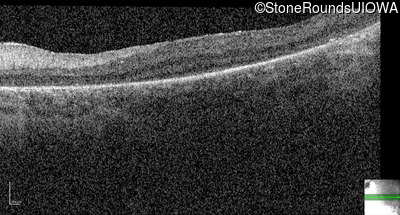

Optical Coherence Tomography - Left -

No Light Perception

Exemplar

Expanded OCT Stack

×